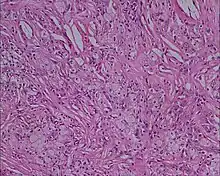

Histologie (Microscopie)

- Infiltrat dermique d'histiocytes géants parfois polynucléés (cellules de Touton) dont le cytoplasme spumeux est chargé de lipides : cholestérol essentiellement